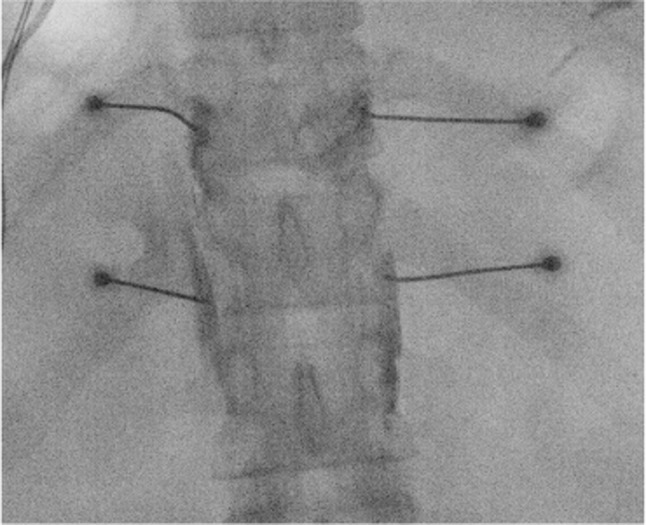

Results: Treatment of abdominal pain in chronic pancreatitis is guided by pancreatic morphology on imaging, although the correlation between pain symptoms and pathoanatomical changes is not always straightforward. Patients with pancreatic duct obstruction are initially offered endoscopic or surgical therapies, while non-obstructive disease is mostly managed medically. Lifestyle changes and psychological support are of particular importance for all chronic pancreatitis patients. Analgesic options range from non-opioid medications to opioids and adjuvant agents. Interventional pain management may consist of radiofrequency treatment of the splanchnic nerves and spinal cord stimulation. To date, there are no randomized trials supporting their efficacy in the treatment of chronic pancreatitis pain, and the recommendation to consider these treatment options is justified by evidence from observational studies. Possible opioid-sparing effects of interventional pain treatments are important to consider because opioid use and dependency are common in chronic pancreatitis patients and associated with worse outcomes. Celiac plexus block is not generally recommended for chronic pancreatitis due to the limited quality of evidence, overall short duration of effect, and invasiveness of the procedure. Central sensitization can impact the effectiveness of invasive treatments.